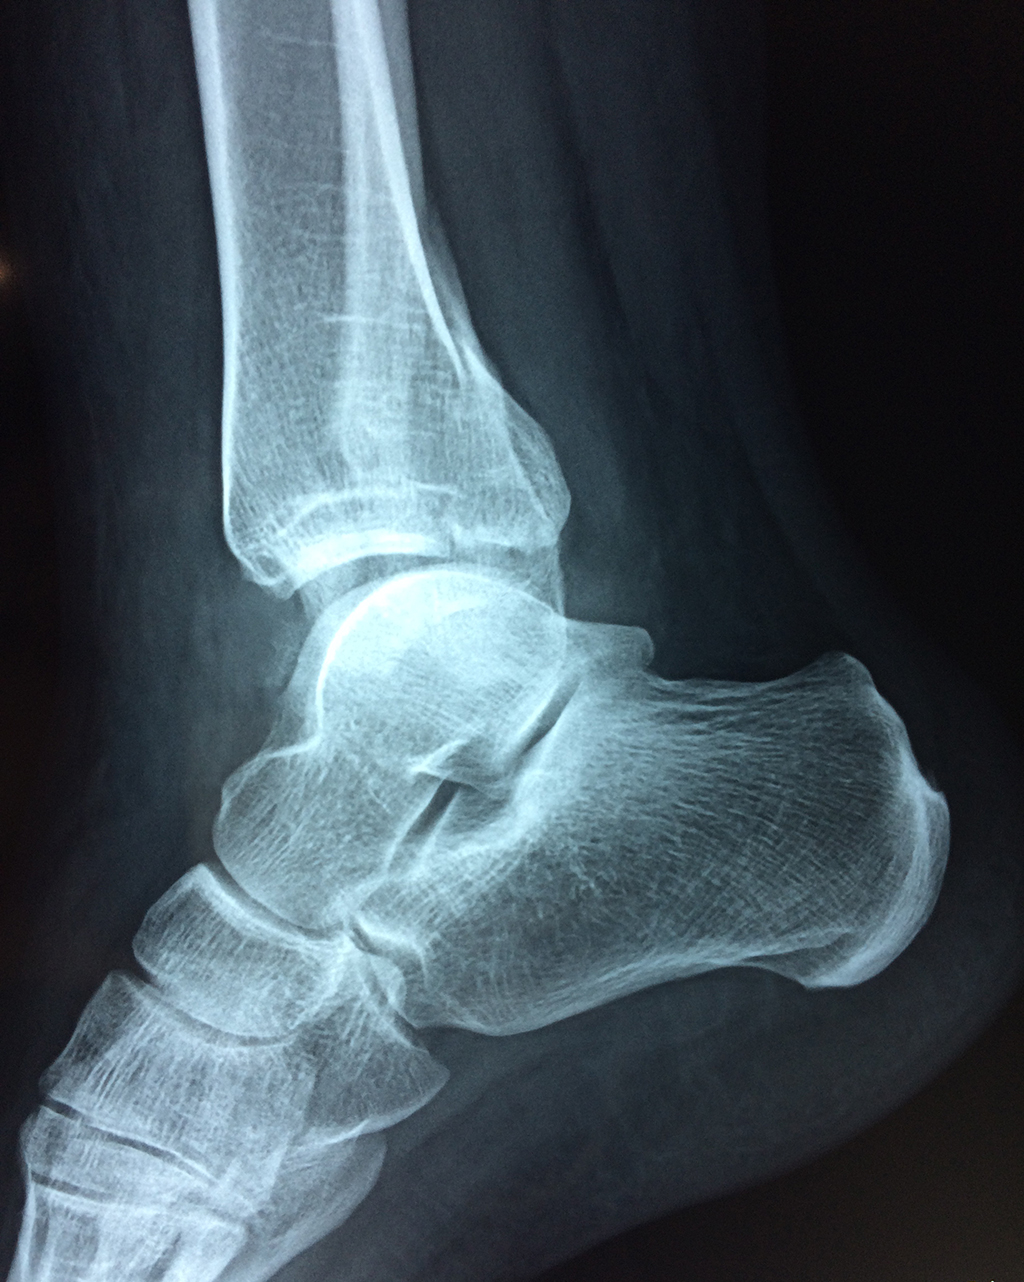

Una fractura de tobillo es la rotura de uno o más de los huesos del tobillo. Estas fracturas pueden ser:

Algunas fracturas de tobillo pueden requerir cirugía si:

- La fractura se extiende hasta la articulación del tobillo (fractura intra-articular).